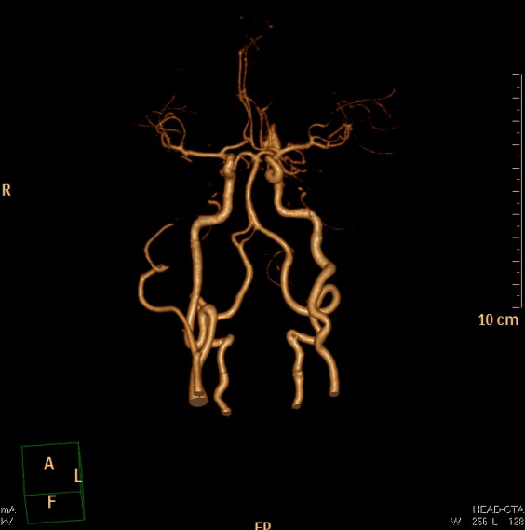

详细了解病情后,家属要求进行手术治疗。在完善相关检查后,由我院神经外五科主任鲁明主刀,在全麻下行左侧颈内动脉颈段动脉瘤切除+血管吻合术,术中显微镜下见颈内、颈外动脉及其分支,颈内静脉、三叉神经下颌支、舌下神经、迷走神经、副神经等,暴露清晰,见约3.5*4cm大小动脉瘤,充分暴露动脉瘤近端及远端颈内动脉;临时夹阻断动脉瘤两端血管,电生理监测;切开动脉瘤,部分切除后,见动脉瘤引流端颈内动脉部分被动脉瘤壁包裹,予以分离,全切动脉瘤;修剪颈内动脉两断端后,予以血管吻合,全程电生理监测未见明显异常;静脉注射吲哚菁绿,荧光显微镜下见吻合处血流通畅,术中出血约600ml,输注红细胞悬液2单位,手术顺利结束。术后患者神志清醒,诉头痛、头晕较前好转,经专科治疗护理,两周后满意康复出院。

术后复查CTA